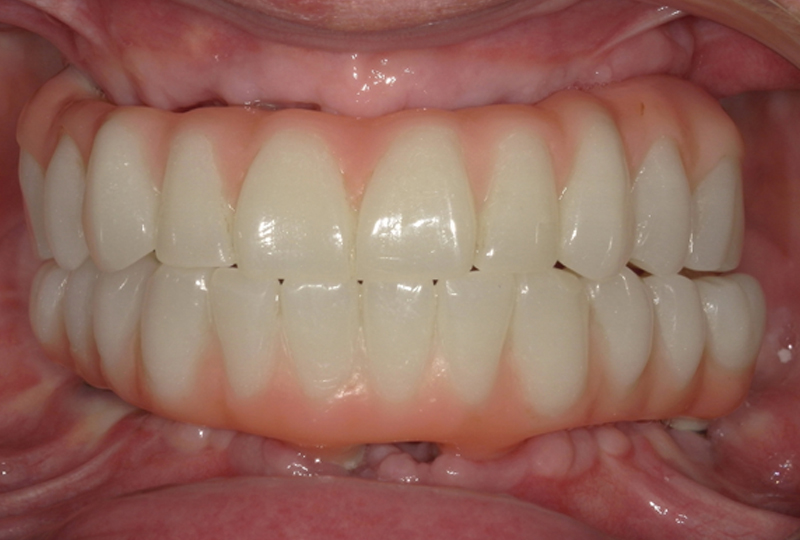

Le protesi definitive venivano prodotte in zirconia multilayer (ZOLID-GEN X 1100±150®, AMANN GIRRBACH) infiltrata e colorata con ceramiche fluide (MIYO®) sia nella parte bianca che in quella rosa. I T-base di connessione venivano incollati nel corpo protesico senza utilizzare nessun modello in gesso di riferimento. Nel terzo e ultimo appuntamento consegnavamo le protesi definitive (Figure 21,22,23).